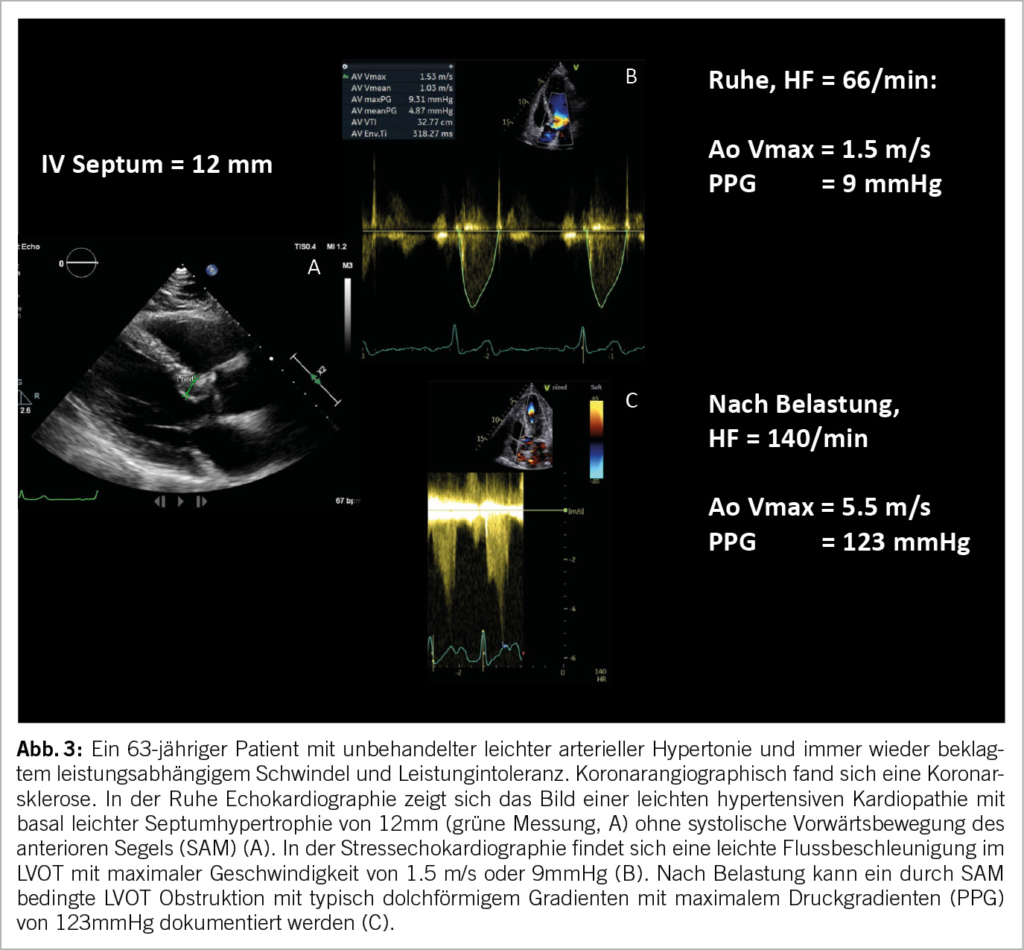

Die SE erweist sich als äußerst nützlich im Rahmen der Abklärung von Dyspnoe unklarer Ätiologie. Neben der Suche nach Ischämie ermöglicht sie gleichzeitig die Identifikation einer belastungsinduzierten höhergradigen diastolischen Dysfunktion oder belastungsinduzierten pulmonalen Hypertonie. Die Ursache der Dyspnoe kann auch auf eine dynamische Obstruktion im linksventrikulären Ausflusstrakt (LVOT) durch eine systolische Vorwärtsbewegung des anterioren Segels (SAM) zurückzuführen sein, was typischerweise bei hypertropher obstruktiver Kardiomyopathie (HOCM) auftritt. Eine weitere häufig anzutreffende Gruppe sind ältere Patienten, die in der Regel ein sigmoidförmiges Septum bei hypertensiver Kardiomyopathie und ein geringeres linksventrikuläres Volumen aufweisen (10) (Abb. 3). Eine weitere, seltenere Ursache der Dyspnoe kann ein unter Belastung auftretendes passageres apikales Ballooning in Patienten mit stattgehabtem Takotsubo Event sein (11).